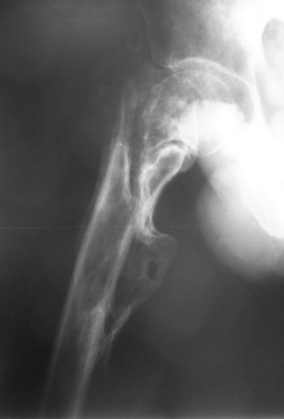

Сросшийся со смещением чрез-подвертельный перелом

Больной Н. 44 года травма 1,5 года назад июнь 2008 года чрез-под вертельный перелом правого бедра. Во время лечения у больного развился алк. делирий, проводилось консервативное лечение перелома.

Беспокоят боли, укорочение конечности. Укорочение 3 см. Ногу поднимает, сгибание ограничено, ротационные движения в полном объеме. На КТ перелом сросся за счет костной мозоли. Что делать?

Протез? Если «да» Можно ли обойтись стандартной ножкой Corail?

Или межвертельная остеотомия?